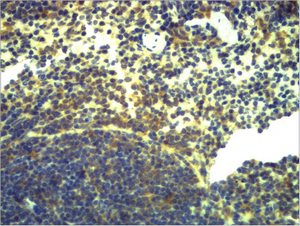

IHC, IF

IHC 1:200-500; IF 1:50-200